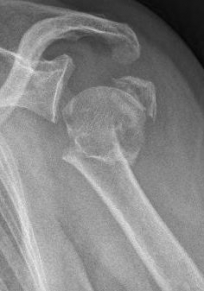

Proximaler Oberarmbruch5Proximaler Oberarmbruch6

Picture: Here is a subcapital upper arm break in a young woman. An angle stable plate osteosynthesis was performed to stabilize the head in correct position to the humeral shaft and shoulder joint. Especially in young patients, We strive to treat non-invasively and as gently as possible. This possibility is often due to the bone quality in young as opposed to older people.